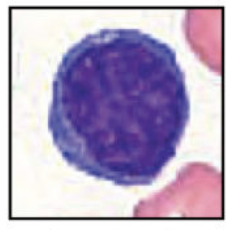

How to identify lymphocytes?

Large nucleus, thin cytoplasm